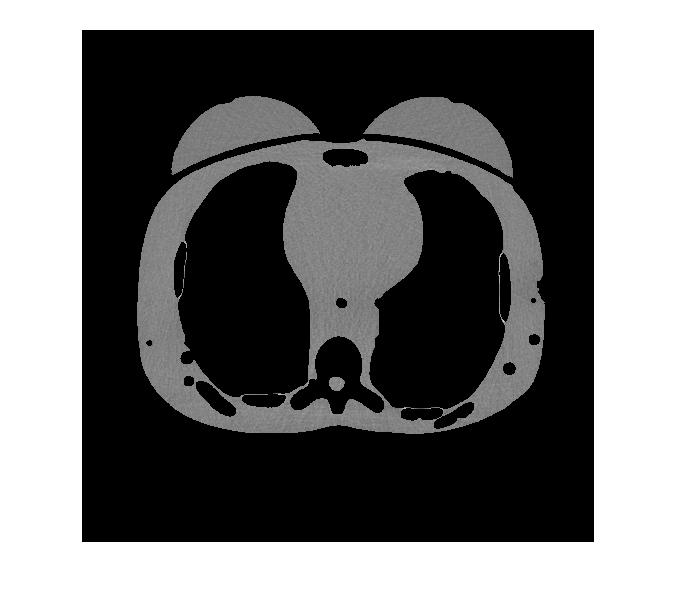

II-C CT Image Visualization

We begin by visually comparing the ROI selected by the WFDM method to that of the baseline method. Fig. 3 demonstrates the baseline thresholding method from Fig. 1 now applied to an image taken from a patient at 48m​Aπ‘šπ΄mA tube current. Fig. 3(a) is the original image scaled to [0,1]01[0,1] and Fig. 3(b) is the mask acquired by thresholding pixel intensities such that [0.4,0.7]=10.40.71[0.4,0.7]=1 and the remaining pixels are set to 00. The ROI shown in Fig. 3(c) results from further narrowing the threshold so that [0.5,0.6]=10.50.61[0.5,0.6]=1 and the remaining pixels are set to 00. In addition, these threshold ranges were chosen empirically, hence the baseline method is not generalizable.

Conversely, applying WFDM to the same CT image shown in Fig. 3(a) and thresholding at [q<IDΒ―4]delimited-[]π‘žΒ―subscriptID4[q<\frac{\overline{\rm I_{D}}}{4}], where IDΒ―Β―subscriptID\overline{\rm I_{D}} is the mean distance in IDsubscript𝐼𝐷I_{D}, results in the mask and corresponding ROI-LV shown in Fig. 4, respectively. Here, we observe the qualitative variations between the original image and the masked ROI-LV image. First, edges, as well as regions of high spatial variation such as the spine, have been removed. Second, the selected regions are not necessarily of the same absolute pixel intensity, as compared with the ROIs shown in Fig.3. Finally, the masked ROI-LV region in Fig. 4(b) is selected by relative thresholding as opposed to fixed intensity thresholding in the baseline method. Thus, the proposed WFDM based ROI-LV masking method is generalizable.

Refer to caption

Figure 4: The same CT image as in Fig. 3(a) after processing with WFDM. (a) A mask ROI-LV and (b) the masked ROI-LV are observed.